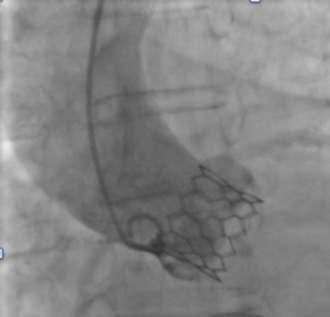

V-shaped hinges on hexagonal frame fold, generating the dense bands on fluoroscopy

Vertical connectors ‘|’ give rise to light bands

Alternating V-folds & vertical connectors give Myval THV a unique ‘Zebra Crossing’ appearance on fluoroscopy for ease of positioning

Alternating V-folds & vertical connectors give Myval THV a unique appearance on fluoroscopy for ease of positioning

Elimination of THV frame parallax promptly ensures visualisation of characteristic dark-light bands

Fluoroscopic images have been dramatized & and may not be in 1:1 ratio